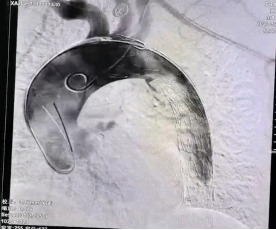

【医讯速览•新闻】第74期:我院心血管内科完成一例主动脉覆膜支架隔绝术